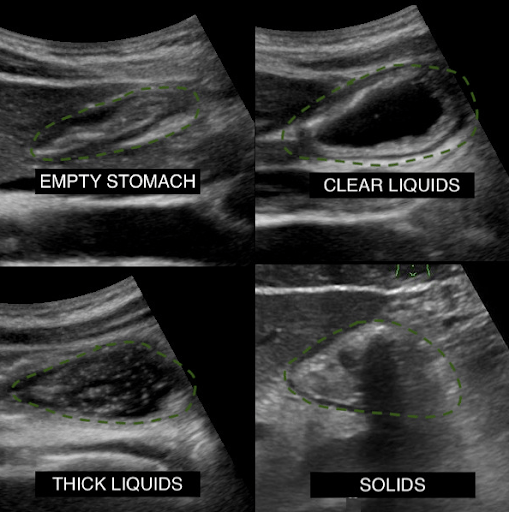

In September 2023, the Journal of BioMed Central Emergency Medicine described a technique to utilize ultrasound to predict aspiration in patients undergoing endotracheal intubation and found a gastric craniocaudal (CC) diameter greater than or equal to 2.35 cm (Sn 88%, Sp 91%) or anteroposterior (AP) diameter greater than or equal to 5.15 cm (Sn 88%, Sp 87%) as predictive of aspiration.

The topic was also systematically reviewed by Howle et al in May 2020 in the gravid and postpartum settings, where antral cross-sectional area cutoffs were recommended in the semi-recumbent (608 mm2) and right lateral semi-recumbent (960 mm2) positions. The evidence further supports that gastric emptying is delayed by term pregnancy, labor, and during the early postpartum period.

Flynn et al. conducted a narrative review of the anatomy of the stomach and adjacent organs, exploring how ultrasound can be utilized to assess gastric content and predict the risk of pulmonary aspiration of gastric contents.

In the pediatric milieu, gastric Point-of-Care Ultrasound has proven valuable for optimizing induction, diagnosing conditions such as foreign bodies and hypertrophic pyloric stenosis, and assisting with confirming nasogastric tube placement. This approach helps avoid delays and minimizes radiation exposure linked to alternative modalities.

The CRNA recognizes that a cross-sectional area less than 10 cm2 (considered reassuring in an average-sized adult) indicates that the stomach is empty, making it safe to proceed with routine IV sedation.

The cross-sectional area of the gastric antrum appears to be 28 cm². Additionally, there is hyperechoic, shadowing material in the gastric antrum, making it challenging to accurately determine the posterior wall. However, the anesthesiologist interprets this as evidence of solid food in the stomach and utilizes the Perlas formula to estimate approximately 350 mL of food and liquid present.